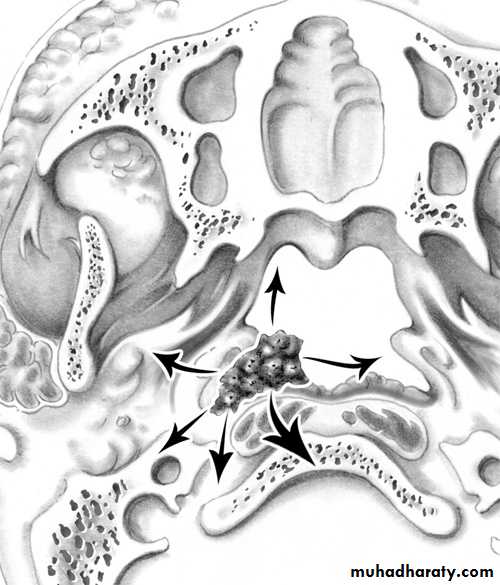

The tumour takes origin from the periosteum on the lateral wall of the nasopharynx close to the sphenopalatine foramen. Extension occurs:

1. Anteriorly to the nasal cavity and ethmoid.

2. Superiorly to the base of the skull.

3. Laterally to the pterygoid fossa, maxillary antrum and orbit.